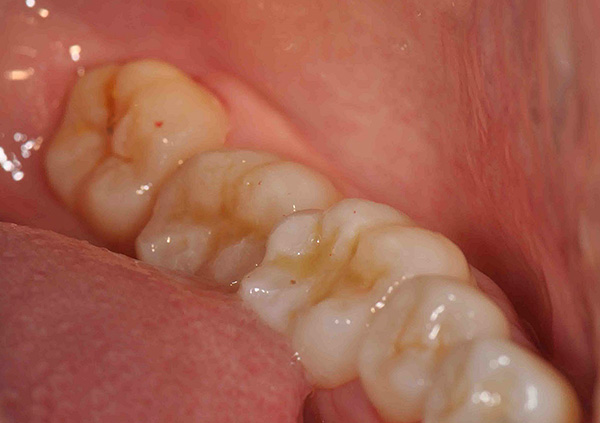

Esempio n. 1: non ci sono stati problemi con la dentizione del dente del giudizio, e si è inserito esattamente senza ferire la mucosa orale, ma sulla sua superficie sono comparsi focolai di carie (masticazione, contatto, ecc.). In questo caso, non è necessario rimuovere il dente del giudizio, ma è consigliabile trattarlo il più presto possibile in modo che il processo carioso non vada più in profondità nella camera della polpa (fino al "nervo").

Tuttavia, anche se la polpa del dente è interessata e non si tratta più della carie, ma della pulpite - anche in questo caso, il dente del giudizio non ha bisogno di essere precipitato affatto, è solo necessario trattare i canali e stabilire un sigillo. Il dente sarà "morto", ma può durare molto, molto a lungo.

La fotografia sotto mostra un esempio di significativa distruzione cariata di un dente del giudizio: